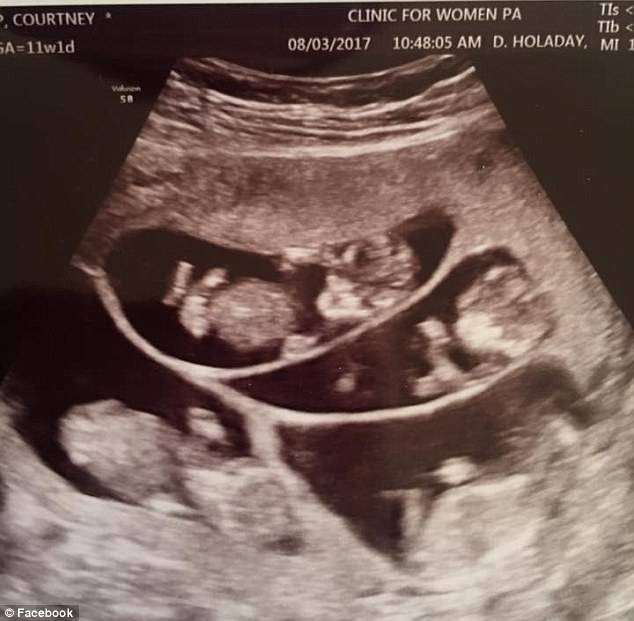

Courtney ed Eric Waldrop sono una coppia americana che, prima di realizzare il loro sogno di avere bambini ha dovuto affrontare diversi aborti. Il loro primogenito Saylor è nato nel 2008, poi però la coppia ha dovuto ricorrere alla fecondazione in vitro per avere altri figli. I loro due gemelli Wale e Bridge ora hanno 5 anni.

Dopo un ultimo aborto spontaneo il medico della coppia ha messo Courtney a basso trattamento di fertilità per impedire che la donna avesse una gravidanza plurigemellare. Durante un controllo però i tecnici hanno sentito 6 battiti nell’utero materno. Una gravidanza di 6 bambini era ad alto rischio, i bambini infatti potevano nascere pre-termine. Anche per la mamma inoltre ci sono dei rischi:

Allo stesso tempo i parti multipli per la fecondazione in vitro sono scesi dal 48% al 32%. Courtney ha tenuto aggiornati famigliari e amici con una pagina su Facebook, a 11 settimane ha scritto: “pregate che il mio appetito mi permetta di mangiare come non ho mai fatto prima”. Sembrava impossibile portare completamente a termine una gravidanza di 6 bambini e la mamma infatti sperava di arrivare almeno a 30 settimane.